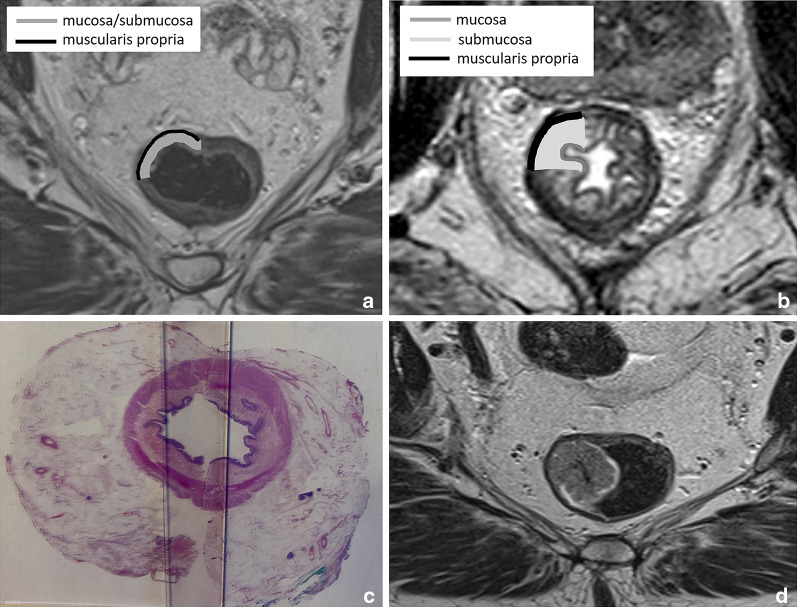

It is important to realise that on a routine T2-weighted MRI, the rectal wall typically has a two-layered instead of three-layered appearance with a total thickness of only 2–3 mm [16]. The mucosa and submucosa are in most cases indistinguishable and seen as a single intermediate signal layer surrounded by a second T2-hypointense layer that represents the muscularis propria (Fig. 2A). The mucosa and submucosa can be recognised as separate layers on MRI in the presence of submucosal oedema (for example, as a result of radiation therapy). In these cases, the submucosa is visualised as a high signal middle layer between the mucosa and muscularis propria (Fig. 2B). The limited visibility of the separate layers of the bowel wall is one of the main reasons why MRI is generally unable to discern T1 from T2 tumours and why these are often reported together on MRI as stage cT1-2 (Fig. 2D), as is also the case in the structured reporting and staging template published by the European Society of Gastrointestinal and Abdominal Radiology (ESGAR) [2].

Fig. 2.

Examples showing the normal two-layered (a) versus oedematous three-layered (b) appearance of the rectal wall on axial T2-weighted MRI and the corresponding cross-sectional wall anatomy at histopathology (c). Figure d shows an example of a 63-year-old male rectal cancer patient with a polypoid tumour staged as cT1-2 considering that the submucosa is not separately visible, making it impossible to determine whether this tumour invades the submucosa (T1) or infiltrates the muscularis propria (T2)